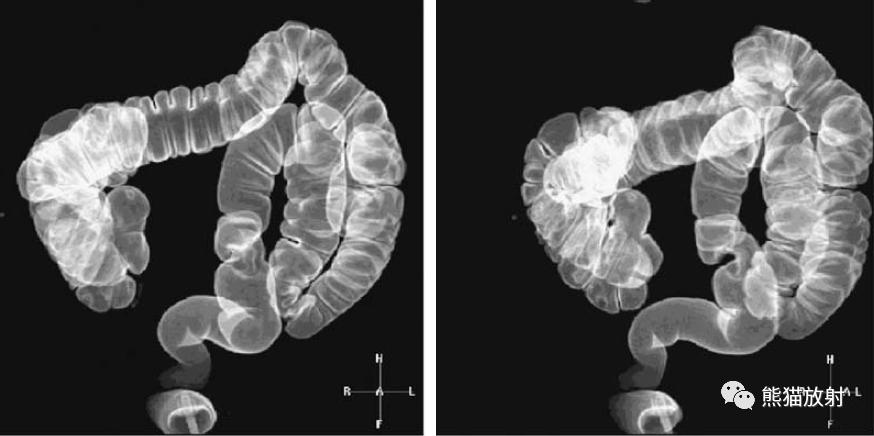

同一患者:结肠肝曲腺癌(黑箭)、升结肠腺瘤(白箭头)

升结肠癌(箭)和横结肠浸润性腺癌(箭头)。